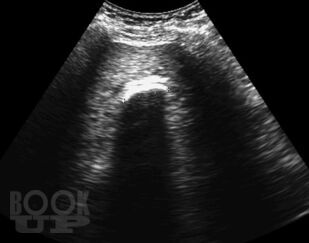

В данном пособии систематизированы сведения об артефактах, которые имеют место при выполнении ультразвуковых исследований. Отдельно рассмотрены эффекты, возникающие в режиме серой шкалы и при выполнении допплеровских исследований. Представлены разработки авторов по изучению допплеровского «мерцающего артефакта» и акустических потоков. Даны рекомендации, позволяющие уменьшить отрицательное влияние артефактов на качество диагностического изображения.